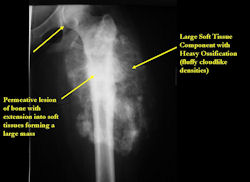

There are 3 radiographic presentations for osteosarcomas, depending upon the amount of osteoid/ossification and calcium deposition:

- Mixed sclerotic and lytic, permeative lesion most common radiographic presentation

- Purely osteoblastic, permeative lesion: dense sclerosis and osteoid production

Conventional osteosarcomas are permeative lesions on plain radiographs (borders of the lesion cannot be clearly delineated)

- Wide zone of transition from lytic/sclerotic areas of tumor to normal bone

- Makes borders of lesion hard to define

- Most conventional osteosarcomas (90-95%) extend through the bone into the soft tissues and form a soft tissue mass outside of the bone